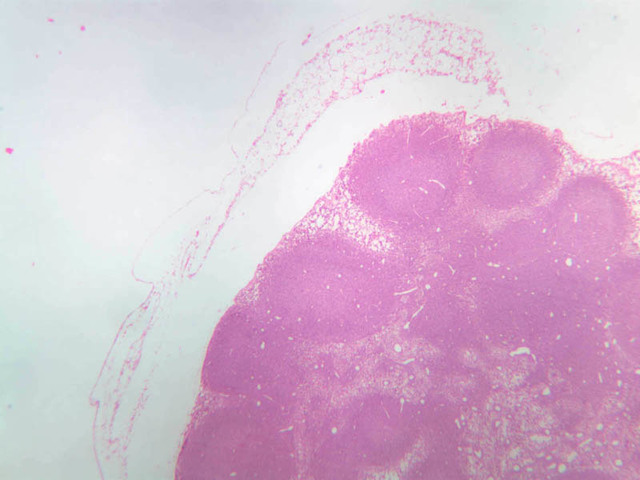

Examine sections B-12 (jejunum, H&E [2.5x, 10x-labeled, 20x, 40x]); B-16, ileum, H&E [2.5x-labeled, 10x, 20x]; B-18, ileum, H&E [2.5x, 10x-labeled, 20x, 40x]; B-20, appendix, H&E [2.5x, 10x-labeled, 20x, 40x-labeled]) and find examples of diffuse lymphatic tissue. Solitary nodules of lymphoid tissue as well as diffuse lymphoid tissue can be found almost anywhere along the gastrointestinal system (this is sometimes called GALT, gut associated lymphoid tissue). The most noted areas with aggregated nodules are found in ileum—Peyer’s Patches (slide B-18, H&E [2.5x-labeled, 10x-labeled, 20x, 40x] [2.5x, 10x, 20x, 40x]), and appendix (slide B-20, H&E [2.5x, 10x, 20x, 40x] [2.5x, 10x,20x, 40x] [2.5x-labeled, 10x, 20x-labeled, 40x]). Peyer's Patch consists of aggregated nodules of lymphoid tissue. Compare the appearance of Peyer's patches to the lymphoid tissue in the appendix. In the appendix, the lymphoid tissue of the appendix appears as a continuous ring of lymphatic tissue in the lamina propria. What features differentiate the appendix from the Ileum?

In lymphatic nodules and nodes the term primary nodule refers to a nodule of homogeneously, tightly packed small lymphocytes. When lymphatic nodules have germinal centers they are called secondary nodules. A germinal center contains lighter staining, "B" lymphocyte precursors. Mitotic figures should be easily spotted in the core of the nodule. Compare these cells with the mass of small more differentiated lymphocytes that surround the germinal center. Some of these lymphocytes are cytokine producing T-Helper cells that are stimulating the proliferation of the lymphoblasts.